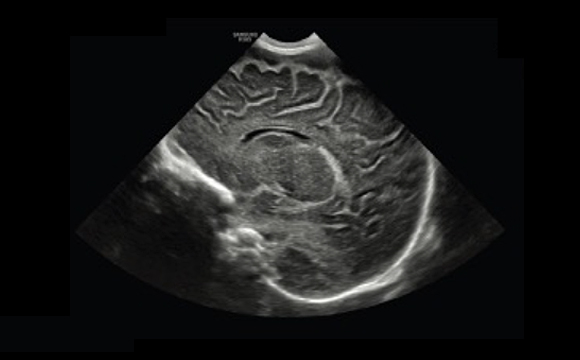

Neonataler Kopf a

Kontrastmittel verstärkter Ultraschall

Die Technologie CEUS+ ¹ nutzt die Eigenschaften von Ultraschallkontrastmitteln und bietet Ihnen die Möglichkeit der Beurteilung von Perfusion und Reflux in Echtzeit. Darüber hinaus bieten Ihnen die Samsung Technologien VesselMax™ und FlowMax™ eine klare Visualisierung von Gefäßen und Blutfluss.

Multimodale Fusionsbiopsien mit hoher Präzision

S-Fusion™ ermöglicht die gleichzeitige Lokalisierung einer Läsion mittels Echtzeit-Ultraschall kombiniert mit anderen volumetrischen Bildgebungsmodalitäten. Ferner wird eine präzise Zielbestimmung bei interventionellen und anderen modernen klinischen Verfahren ermittelt. Die neue Auto-Registrierung von Samsung hilft bei der schnellen und präzisen Fusion der Bilder für hohe Effizienz.